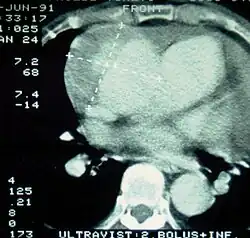

| Computed tomography (CT) | Legend |

| Disección aórtica tipo A de Stanford 1 aorta ascendente, cierto Lumen - 2 Lumen falsa - 3 arteria pulmonar 4 aorta torácica descendente - 5 vértebra torácica | |

La Angiografía de Tórax por Tomografía Computarizada (Angio-TC de Tórax) es una prueba no invasiva de rápido acceso cuyo objetivo es dar una vista tridimensional de la aorta. Estas imágenes son producidas rápidamente, teniendo que cortar rebanadas delgadas del pecho y el abdomen, combinados en el ordenador para crear la sección transversal. A fin de delinear la aorta a la precisión necesaria para hacer el diagnóstico correcto, un material de contraste yodado se inyecta en una vena periférica. El contraste es inyectado y el análisis realizado utilizando un método de seguimiento.

Corresponde al Gold Standard para el diagnóstico de Disección Aórtica, con una sensibilidad de 96 - 100% y una especificidad de 96 a 100%. Las desventajas incluyen la necesidad de material de contraste yodado y la necesidad de estar disponible en un centro asistencial de alta complejidad.